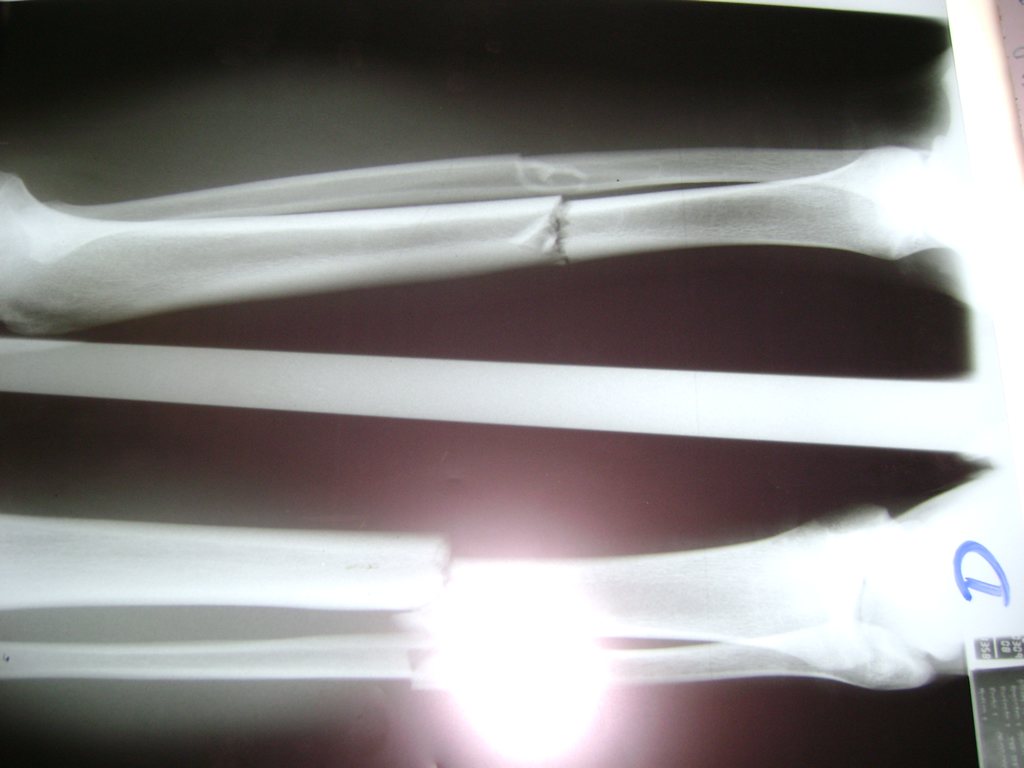

Cirugía de Tibia y Peroné

Aunque cada uno de estos huesos puede fracturarse por separado, normalmente la rotura es una lesión que se produce de forma conjunta

La mayor parte de las roturas implican a la parte proximal del hueso (parte del hueso próximo a la rodilla) o a la parte distal (parte del hueso cerca del tobillo).

Debido a la fina cobertura de piel que recubre la tibia y el peroné, las fracturas generalmente son abiertas, es decir, el hueso roto rasga la piel, atravesándola. Las fracturas de tibia y peroné generalmente se producen por un fuerte impacto o torsión.